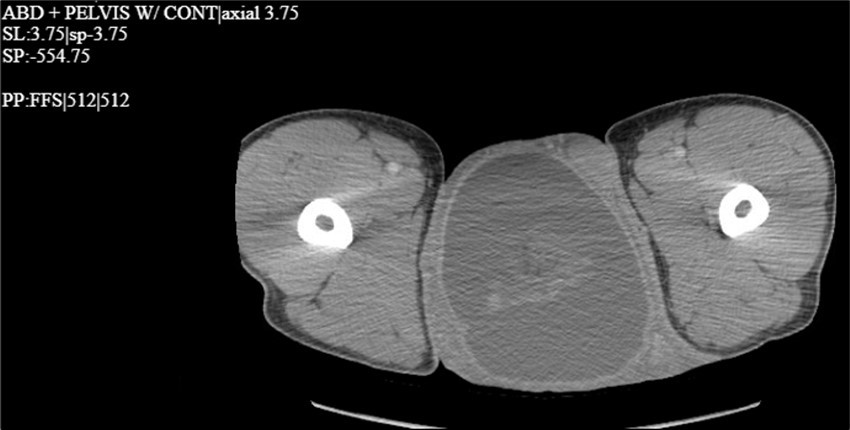

A 34-year-old male presented to the Emergency Department with complaints of large right-sided scrotal swelling, accompanied by scrotal discomfort. The patient’s past medical history was remarkable for a right-sided inguinal hernia, which had been present for several years and was repaired via right open herniorrhaphy with mesh placement three months prior. Physical examination prior to the herniorrhaphy revealed a large inguinoscrotal swelling, measuring 5 inches by 6 inches. During the herniorrhaphy, a very large hernia sac was encountered that could not be fully dissected from the cord structures and required placement of two large meshes; however, the testicles were successfully reduced back into the scrotum. Ultrasound of the right testicle revealed a large hypoechoic space with a complex collection and posterior displacement of the testicle, indicating a possible hydrocele (Figure 1, Figure 2, Figure 3, Figure 4). The patient was taken to the operating room for a right hydrocelectomy. During the procedure, it was noted that the penis was buried within the scrotal swelling, necessitating the placement of a Foley catheter to identify surrounding structures. Upon incision through the Dartos fascia, significant fibrotic tissue and fluid were encountered, making it difficult to maneuver around the hydrocele sac. Upon incising the hydrocele sac, a large collection of thick, dark brown fluid resembling old blood clots was immediately aspirated. Approximately 2 liters of fluid were drained from the sac. After identifying the testicle and cord structures, the proper placement of the testicle within the scrotum was verified. Due to excessive scrotal skin, a scrotoplasty was performed prior to suturing the scrotal skin and fascia (Figure 5). The postoperative hospital course was unremarkable. The patient was discharged with plans to return to the clinic for follow-up with the surgeon.

Figure 4.CT scan with contrast of the thigh region in the coronal plane with testicular swelling noted in between the thighs.